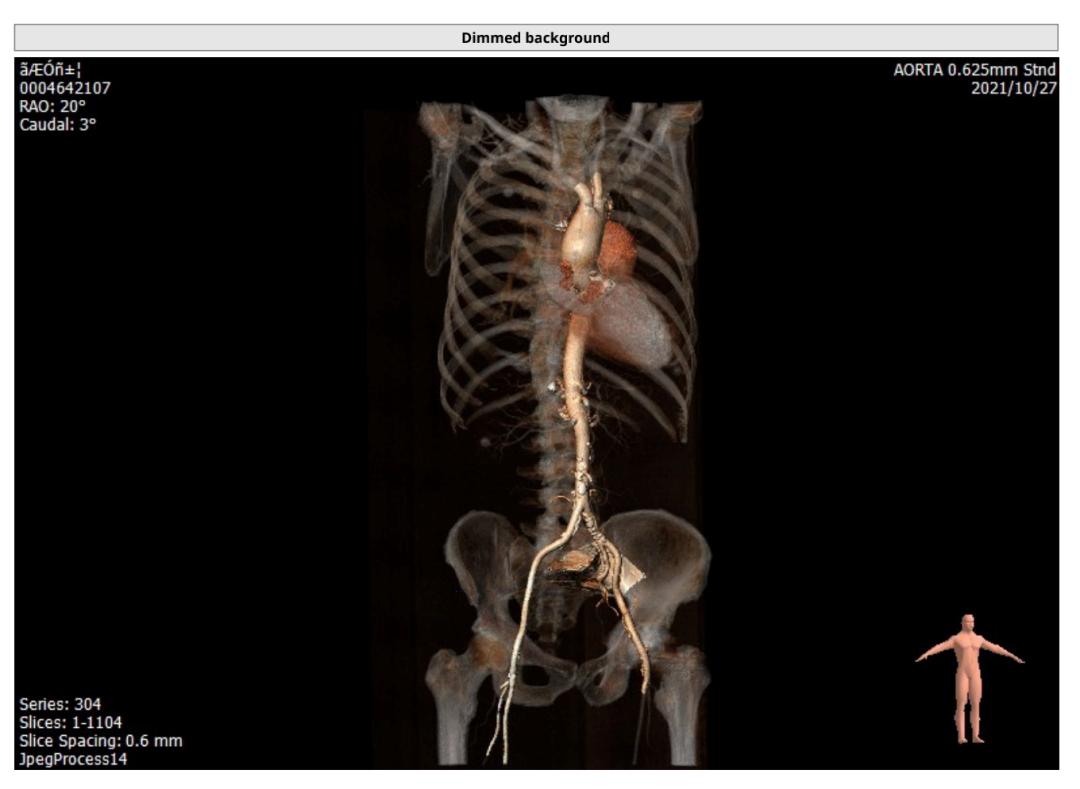

主动脉CT

主动脉根部及瓣环形态

瓣膜不同钙化程度,及形态

瓦氏窦瘤形态

入路条件